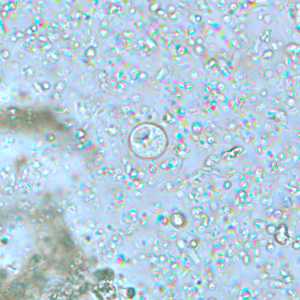

Endolimax nana cysts in concentrated wet mounts.

Figure A: Cyst of E. nana in a direct wet mount, viewed under differential interference contrast (DIC) microscopy.